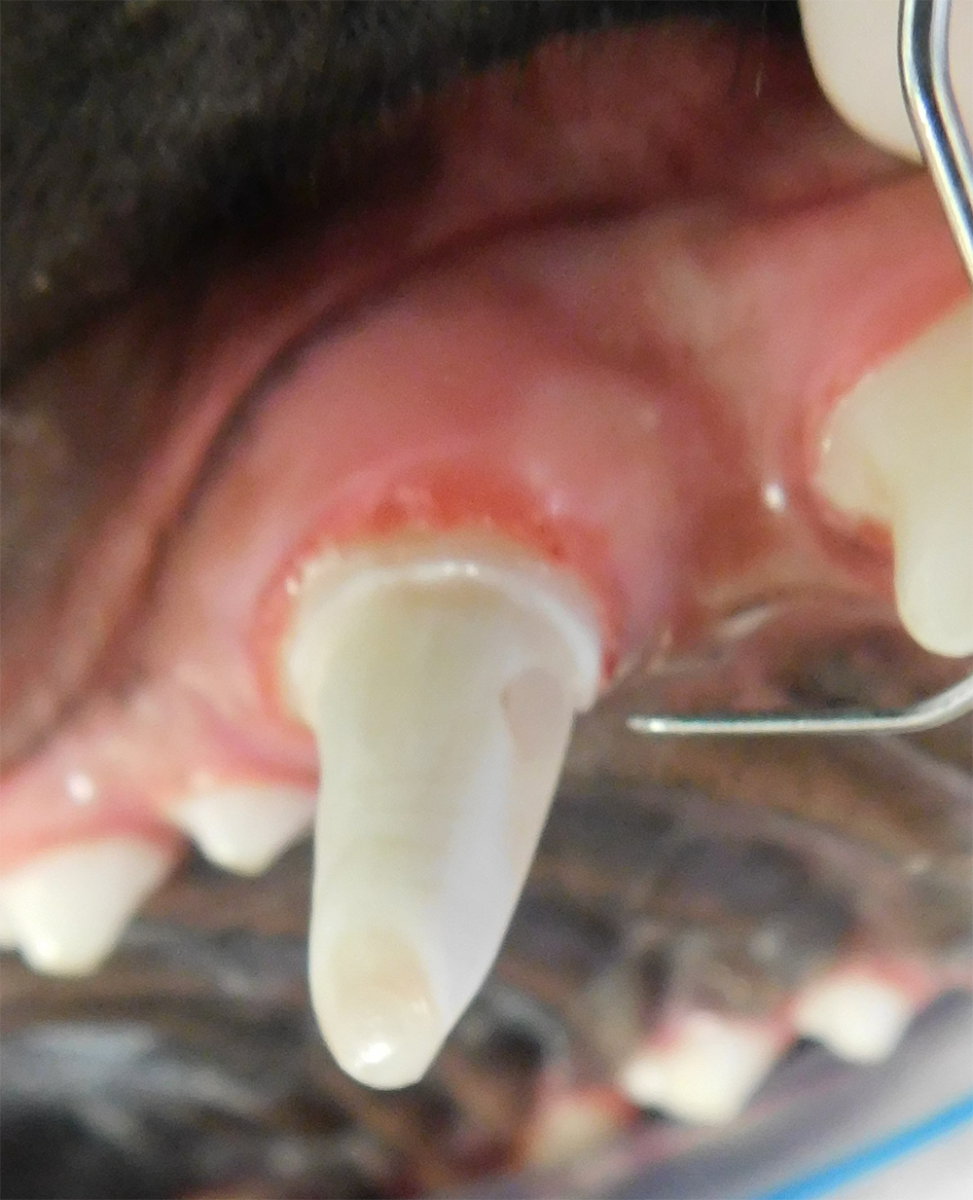

Repair of Maxillofacial Fracture

Pets can be involved in trauma that can cause fractures to their head, teeth, and jaw bones. Correctly repairing these fractures is extremely important for your pet to have normal function of their mouth. If a jaw fracture is allowed to heal in an abnormal position, your pet may have great difficulty chewing and can be in significant pain. Many fractures can be successfully treated with minimally invasive oral procedures, but more complicated cases may require bone plating techniques. The Center offers cone beam CT imaging which provides extremely detailed images of the bones of the head and skull. Advanced imaging with CBCT facilitates selection of the best surgical technique to get your pet back to eating and comfort as soon as possible.